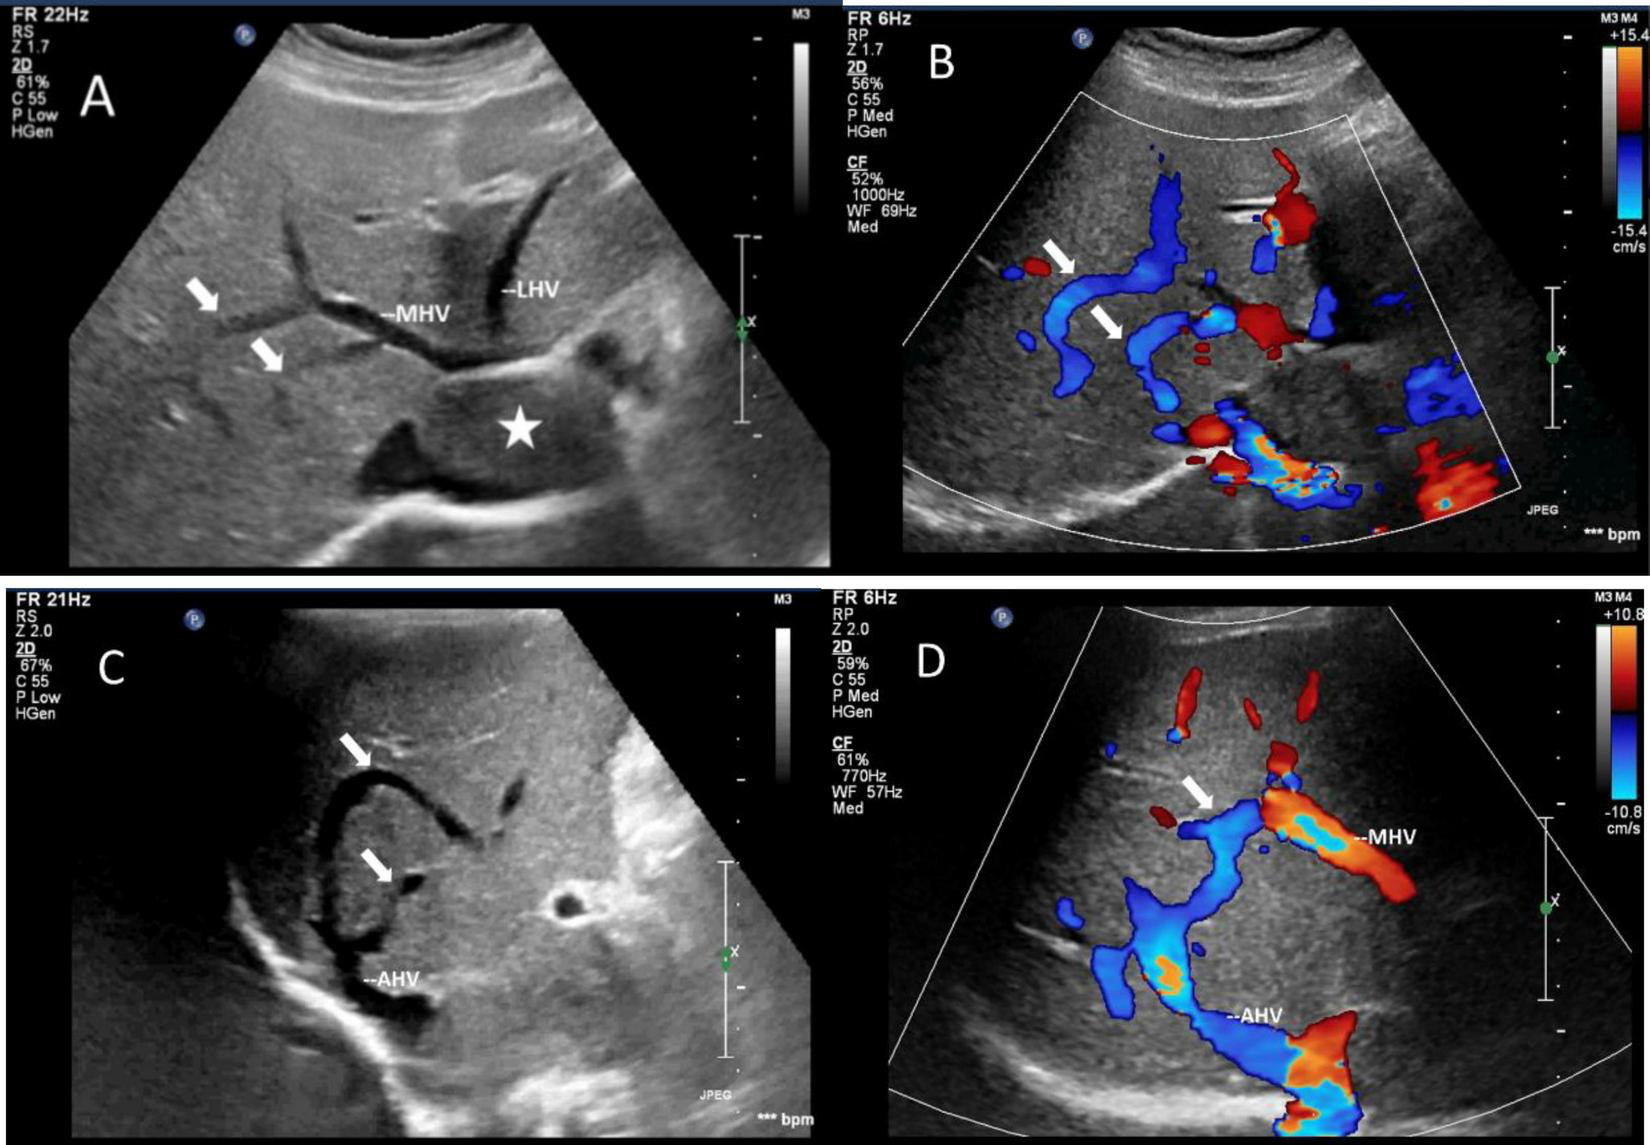

FIGURE 5

Images of collateral circulation between hepatic veins on greyscale and color Doppler sonography. White arrows indicated the collateral veins. (A,C) Gray-scale images displayed the collateral veins connecting MHV and the dilated accessory hepatic vein in the posterior right lobe from various perspectives. (B,D) Color Doppler blood flow images illustrated the blood flow within the collateral veins from different angles. The blood flow direction was observed to move from MHV toward the dilated accessory hepatic vein, ultimately draining into the inferior vena cava. The asterisk denoted the presence of a tumor. LHV, left hepatic vein; MHV, middle hepatic vein; AHV, accessory hepatic vein.